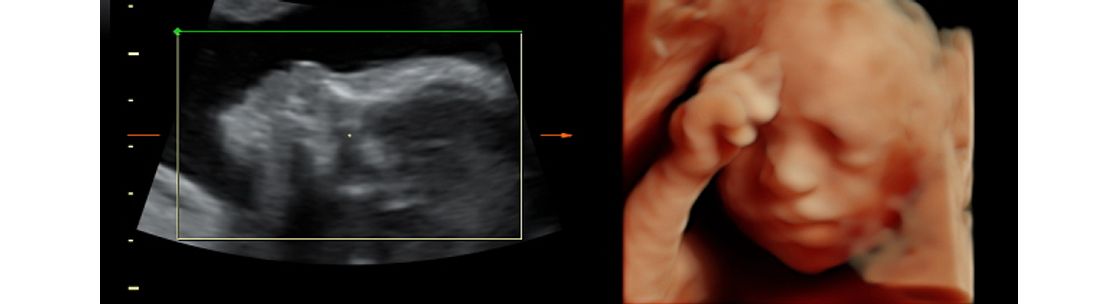

Hampton Roads Moms Getting A Peek Of Joy 3d 4d Ultrasound In

Healthy Innovation Virginialiving Com